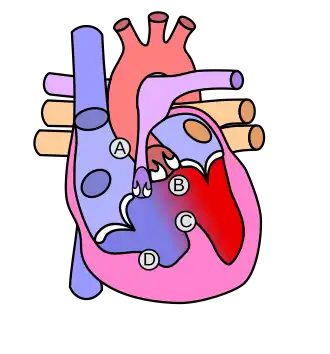

Heart with tetralogy of fallot A: Pulmonary stenosis; B: Overriding aorta; C: Ventricular septal defect (VSD); D: Right ventricular hypertrophy

"Tetralogy" denotes four parts, here implying the syndrome's four anatomic defects.[2] This is not to be confused with the similarly named teratology, a field of medicine concerned with abnormal development and congenital malformations (including tetralogy of Fallot). Below are the four heart malformations that present together in tetralogy of Fallot:

Pulmonary Infundibular Stenosis A narrowing of the right ventricular outflow tract. It can occur at the pulmonary valve (valvular stenosis) or just below the pulmonary valve (infundibular stenosis).[4] Infundibular pulmonic stenosis is mostly caused by the overgrowth of the heart muscle wall (hypertrophy of the septoparietal trabeculae),[42] however, the events leading to the formation of the overriding aorta are also believed to be a cause. The pulmonic stenosis is the major cause of the malformations, with the other associated malformations acting as compensatory mechanisms to the pulmonic stenosis.[43] The degree of stenosis varies between individuals with TOF and is the primary determinant of symptoms and severity. This malformation is infrequently described as sub-pulmonary stenosis or subpulmonary obstruction.[44]

Overriding aorta An aortic valve with biventricular connection, that is, it is situated above the ventricular septal defect and connected to both the right and the left ventricle. The degree to which the aorta is attached to the right ventricle is referred to as its degree of "override." The aortic root can be displaced toward the front (anteriorly) or directly above the septal defect, but it is always abnormally located to the right of the root of the pulmonary artery. The degree of override is extremely variable, with 5–95% of the valve being connected to the right ventricle.[42]

Ventricular septal defect (VSD) A hole between the two bottom chambers (ventricles) of the heart. The defect is centered around the most superior aspect of the ventricular septum (the outlet septum), and in the majority of cases is single and large. In some cases, thickening of the septum (septal hypertrophy) can narrow the margins of the defect.[42]

Right ventricular hypertrophy The right ventricle is more muscular than normal, causing a characteristic boot-shaped (coeur-en-sabot) appearance as seen by chest X-ray. Due to the misarrangement of the external ventricular septum, the right ventricular wall increases in size to deal with the increased obstruction to the right outflow tract. This feature is now generally agreed to be a secondary anomaly, as the level of hypertrophy tends to increase with age.[45]